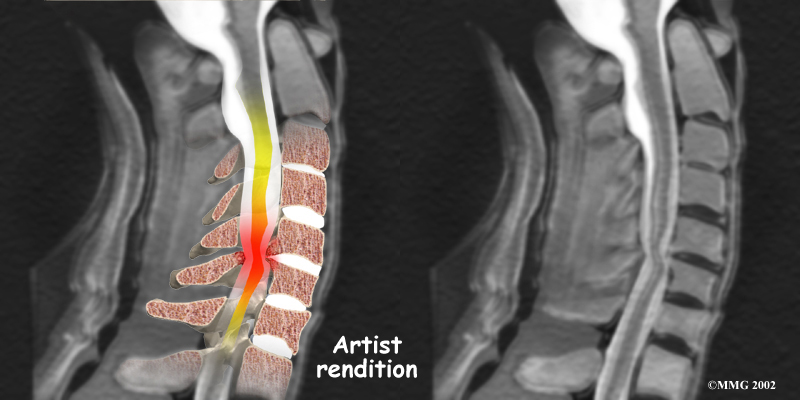

The magnetic resonance imaging (MRI) scan uses magnetic waves to create pictures of the cervical spine in slices. The MRI scan shows the cervical spine bones, as well as the soft tissue structures such as the discs, joints, and nerves.

MRI scans are painless and don't require needles or dye. The MRI scan has become the most common test to look at the cervical spine after X-rays have been taken.